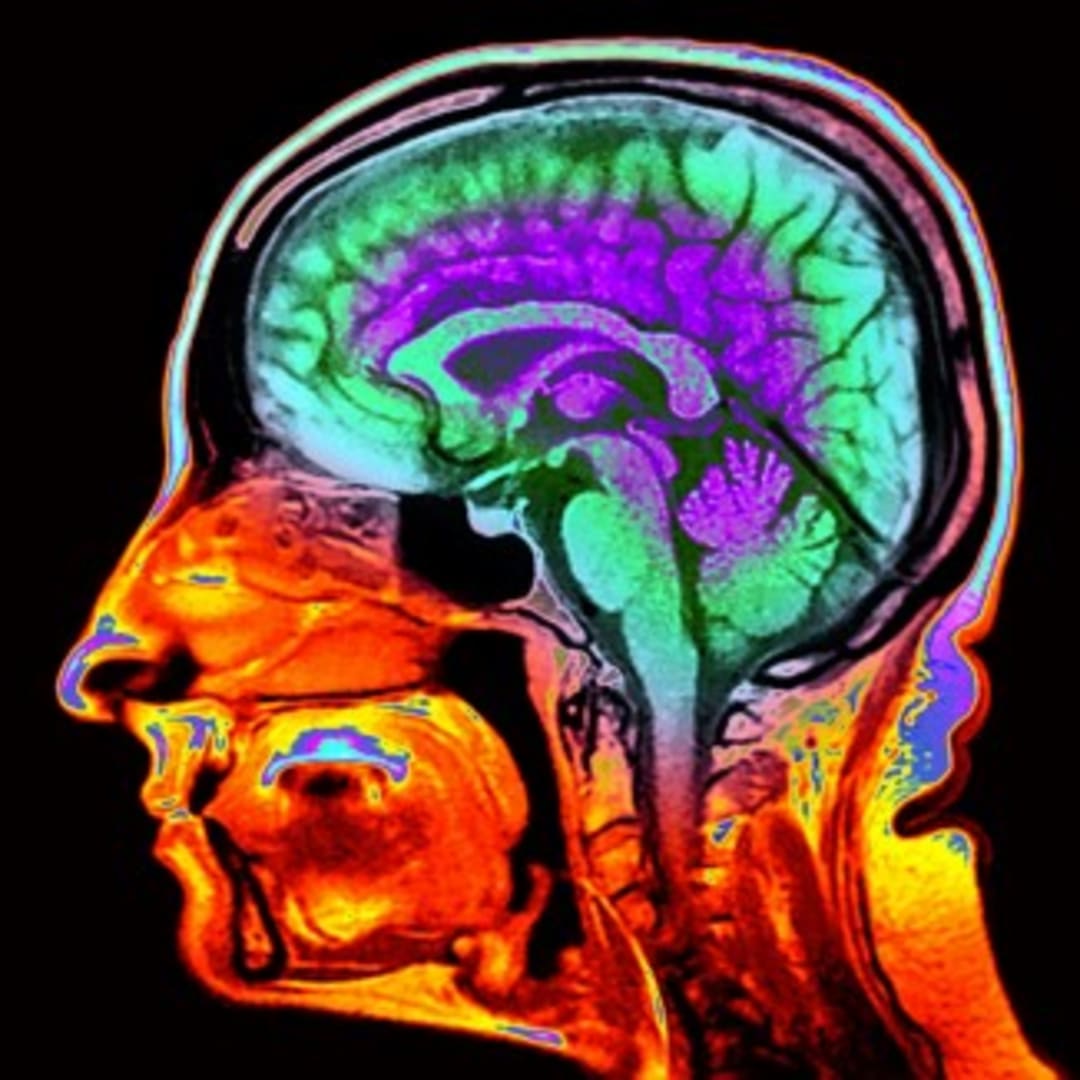

Courtesy of NatureMagazine

Dunedin, New Zealand - Para peneliti telah menemukan bahwa gambar otak standar dari pemindaian MRI dapat digunakan untuk melihat seberapa cepat seseorang mengalami penuaan biologis. Ini sangat penting karena usia kronologis seseorang tidak selalu menunjukkan kondisi sebenarnya bagaimana tubuh dan otak menua.

Faktor utama yang diamati adalah ketebalan lapisan korteks serebral dan seberapa banyak materi abu-abu yang dimiliki otak. Kedua fitur ini telah terbukti bisa membantu memprediksi penurunan kemampuan berpikir dan mengingat, serta risiko penyakit dan kematian di masa depan.